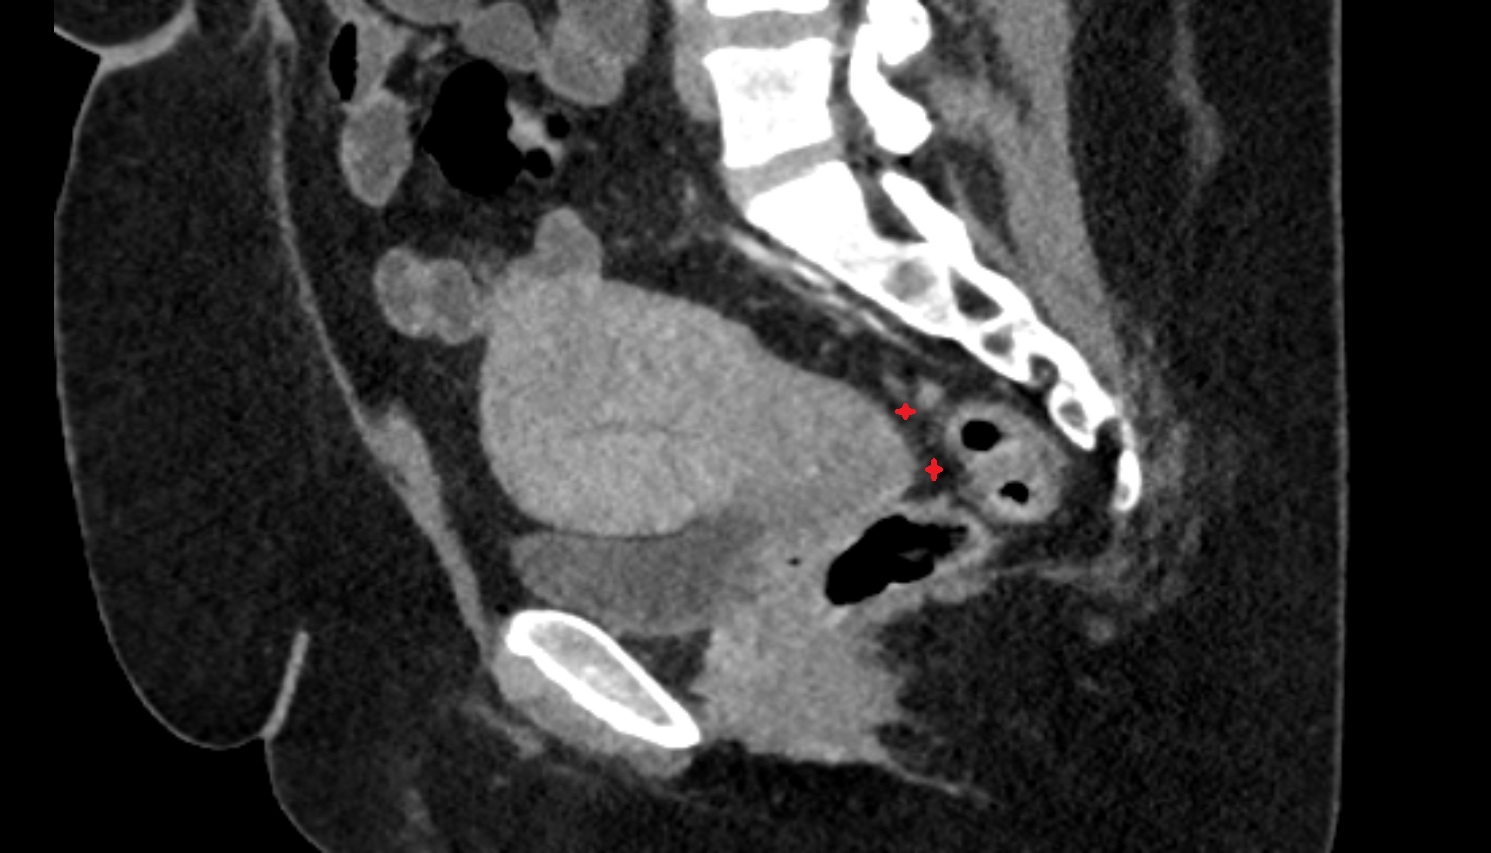

- Uterus

- Cervix of uterus

- Vagina

- Rectouterine pouch (pouch of Douglas)